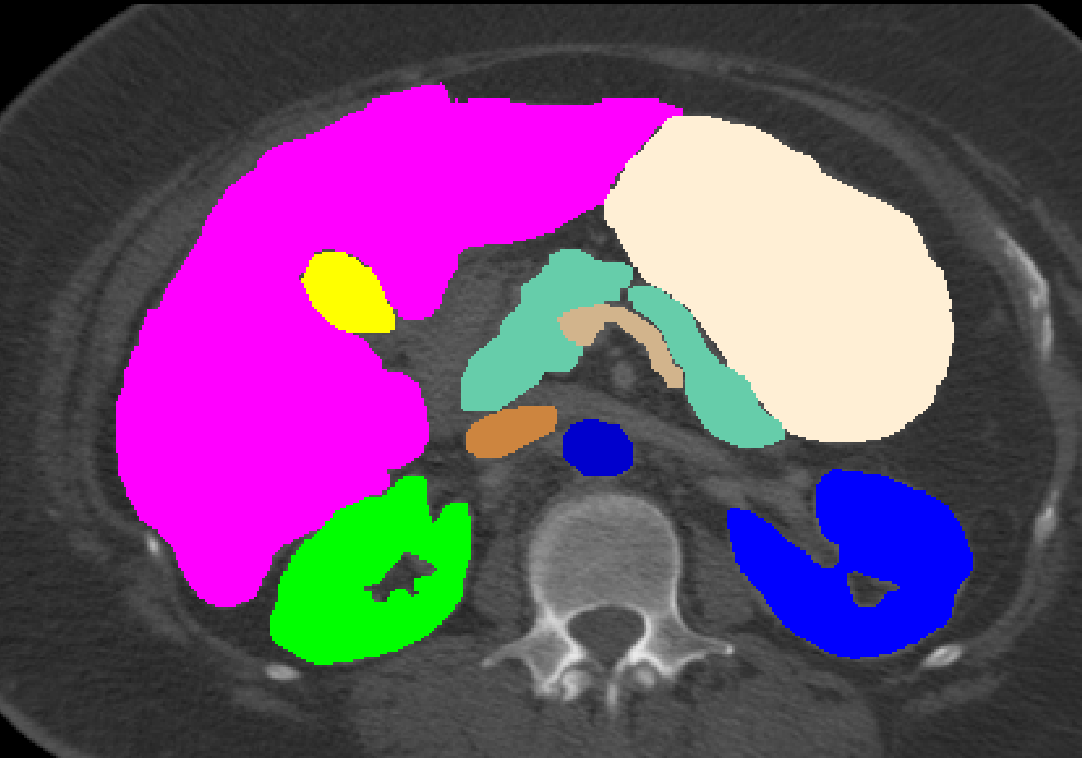

Manual Labels for Verification. We design a mechanism to validate these collected labels by humans. To do so we collect manual labels from 3000 2D image from 300 MRI samples for 10 abdominal organs (UKBOB-manual). These manual labels (see examples in Figure 2) act as a validation for the large UKBOB dataset. On these labels, the UKBOB automatic labels obtain an average Dice Score of 0.891 (see Table 3). Furthermore, we verify the spine labels of UKBOB using previously collected manual labels of 200 3D spine labels [5]. We show an example in Figure 1 and we see how the new collected labels match the manual labels in the spine with a total Dice score of 0.811, indicating accurate labels. We discuss in Section 5.1 another mechanism for verifying the labels by zero-shot generalization of trained models to other similar datasets that has manual labels.

Manual Verification. In Table 3 we validate the quality of the UKBOB labels and the organ quality control against manual spine annotation from [5] and our manually annotated 11 abdomen UKBOB organs (UKBOB-manual). Even without any filtration, UKBOB labels are precise, achieving Dice score of 0.811 and 0.873 on manual spines and UKBOB-manual respectively. We Also show that our SOLF filtering approach (when ) increases Dice score by 0.056 compared to no filtering on the spine labels and by 0.018 on the labelled abdomen organs. We also show standard inter-quartile range filtering (IQR) [30] for comparison.